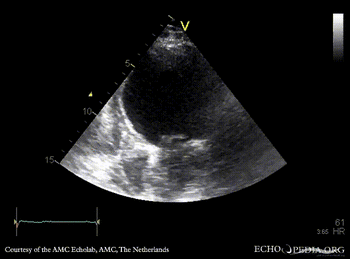

E00705.gif E00706.gif

PLAX: dilated left ventricle, reduced systolic function PSAX